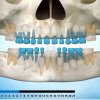

Esimeste molaaride (purihammaste) lõikumine. 1. molaaride ektoopilise lõikumise jälgimine. Ülemised ja alumised esimesed purihambad e. molaarid lõikuvad orienteeruvalt 6-7-aastaselt piimahammaste rea lõppu. Enamasti lõikuvad samanimelised jäävhambad paaridena. Normaalne lõikumise järjekord...